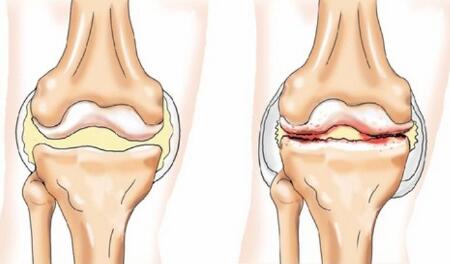

Врачи отмечают, что сабельник, известный своими целебными свойствами, активно используется в народной медицине. Это растение обладает противовоспалительными, обезболивающими и укрепляющими свойствами, что делает его полезным при различных заболеваниях. Специалисты рекомендуют применять сабельник для лечения артритов, остеохондроза и других заболеваний суставов, так как он способствует уменьшению болевого синдрома и улучшению подвижности. Кроме того, сабельник может помочь при заболеваниях печени и почек, благодаря своим детоксикационным свойствам. Однако врачи подчеркивают, что перед началом применения препаратов на основе сабельника необходимо проконсультироваться с медицинским специалистом, чтобы избежать возможных противопоказаний и побочных эффектов.

Сабельник, известный своими целебными свойствами, привлекает внимание как традиционных целителей, так и современных медиков. Люди отмечают его эффективность при лечении заболеваний суставов, таких как артрит и остеохондроз. Экстракты сабельника обладают противовоспалительными и обезболивающими свойствами, что делает их популярными в народной медицине. Многие пациенты делятся положительным опытом применения настоев и мазей на основе этого растения, отмечая значительное облегчение симптомов. Кроме того, сабельник используется для улучшения обмена веществ и детоксикации организма. Однако, несмотря на положительные отзывы, важно помнить о необходимости консультации с врачом перед началом лечения, чтобы избежать возможных противопоказаний и побочных эффектов.

Лечебное действие мази

Аптечная мазь с Сабельником используется для снятия болей разной интенсивности в суставах. Препарат воздействует на воспалительный процесс и понижает его. При длительной терапии мазь восстанавливает поврежденные ткани и участвует в процессе регенерации. Активнодействующий компонент может выводить лишние соли из суставов и улучшать их общее состояние.

Благодаря эффективным противовоспалительным и обезболивающим свойствам мазь Сабельника начала применяться для лечения болезней суставов. Врачи назначают препарат в таких случаях:

- Реактивный артрит;

- Лечение артроза;

- Вторая стадия остеохондроза;

- Терапия ревматоидного артрита;

- Снятие симптомов остеохондропатии.

Только одна мазь Сабельника не сможет полностью вылечить от этих заболеваний. Поэтому врачи назначают комплекс препаратов для эффективной терапии.

Как сабельник помогает восстановить суставы?

Сабельник эффективно снимает боль в суставах, вызванную воспалительными процессами, такими как артрит, артроз и ревматизм. Растение помогает уменьшить острую или ноющую боль, особенно усиливающуюся при движении или нагрузках на суставы.